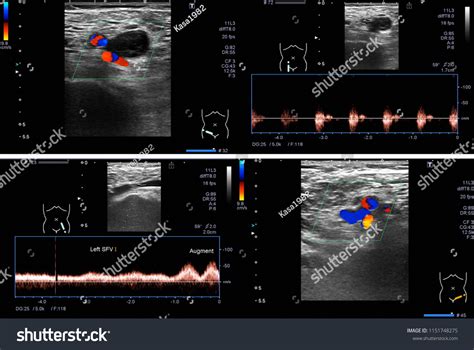

So, let’s break down the magic behind Doppler ultrasound and its role in diagnosing Deep Vein Thrombosis (DVT) . At its core, ultrasound technology uses high-frequency sound waves that bounce off tissues and structures in the body, and then return to a transducer, which converts these echoes into an image. Pretty neat, right? Now, the ‘Doppler’ aspect is where it gets really interesting for DVT. This specialized function adds the ability to detect the movement of red blood cells. As these cells flow through your veins, they cause a change in the pitch or frequency of the returning sound waves – this is known as the Doppler effect. If there’s a blood clot (thrombus) present in a deep vein, it acts like a roadblock. This obstruction will alter the normal, smooth flow of blood, causing turbulence or even complete cessation of flow in that area. The Doppler ultrasound machine can pick up these changes in blood flow velocity and direction. A normal vein will show a continuous, predictable flow pattern. However, a vein with a DVT will often show absent flow, sluggish flow, or flow that is not completely compressible when the transducer is applied. The radiologist or sonographer will carefully examine the major deep veins, particularly in the legs, looking for these tell-tale signs. They’ll use the transducer to apply gentle pressure, which helps to compress the normal, elastic veins. If the vein can be compressed, it usually means there’s no significant clot. But if the vein remains uncompressible, it’s a strong indicator of DVT. The ability of Doppler ultrasound to provide this real-time, dynamic information about blood flow is what makes it such a powerful diagnostic tool for DVT. It’s non-invasive, readily available, and generally considered very safe, making it the preferred method for clinicians.